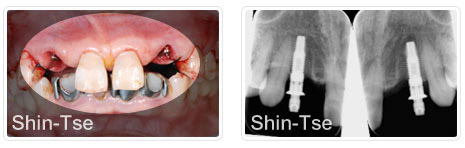

植牙前   植牙後X光片

將不對稱牙齒拔除後,立即微創植牙。